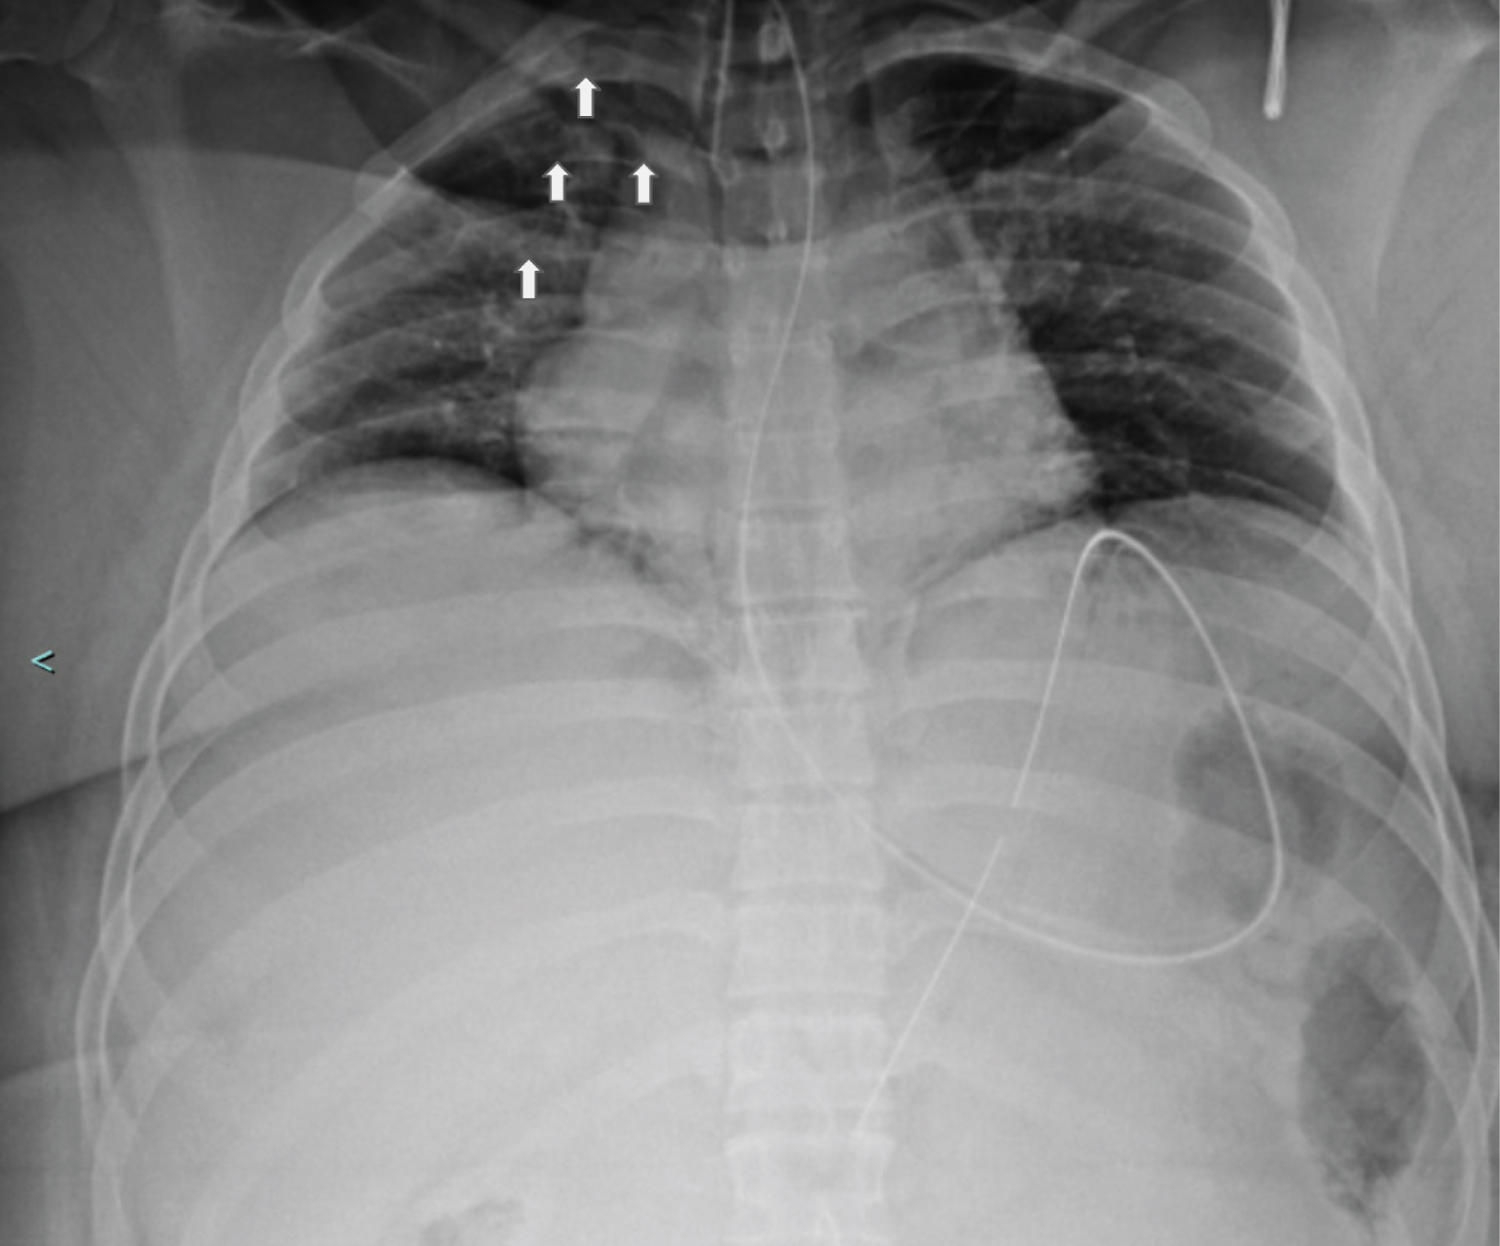

X-Ray eight hours later showed subcutaneous emphysema of the right chest wall (Figure 2A), with corresponding computed tomography (CT) showing worsening of the right-sided pneumothorax, as well as an intercostal pleurocutaneous fistula along the anterior superior chest wall (Figure 2B). A right-sided chest tube was then placed, and daily X-rays were performed to assess for resolution of the fistula (Figure 3). Within 12 hours improvement was seen, and within 36 hours the subcutaneous emphysema was nearly resolved (Figure 4).

Figure 3: Portable chest X-ray taken 12 hours after chest tube placement shows improvement of right-sided subcutaneous emphysema.

Figure 4: Portable Chest X-ray 36 hours after chest tube placement shows near total resolution of the right-sided subcutaneous emphysema.